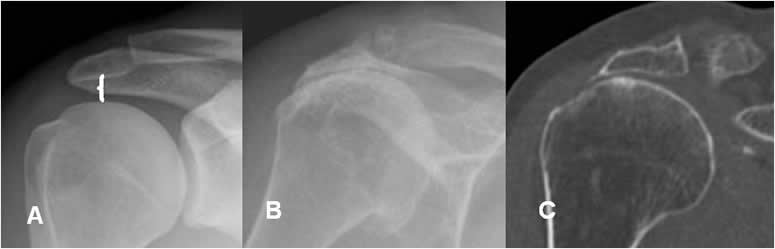

Espacio articular glenohumeral:

Es la distancia entre el borde medial del húmero y la parte anterior de la glenoides.

Su valor normal es menor de 6 mm y se aumenta en casos de luxación posterior. (1, 10).

(Fig 44).

Fig 44. Luxación posterior.

A: Rx AP. Espacio glenohumeral normal.

B: Rx AP. Aumento del espacio glenohumeral, por luxación posterior.

Espacio acromiohumeral:

Es la distancia vertical entre el borde inferior del acromión y el superior de la cabeza del húmero. El valor normal oscila entre 6 y 14 mm y disminuye en los casos crónicos, de ruptura del manguito rotador. (1, 11). (Fig 45).

Fig 45. Ruptura del supraespinoso.

A: Rx AP. Espacio acromiohumeral normal.

B: Rx AP y C: TAC reconstrucción coronal. Cambios degenerativos con pérdida del espacio acromiohumeral y esclerosis asociada, por ruptura crónica del supraespinoso.